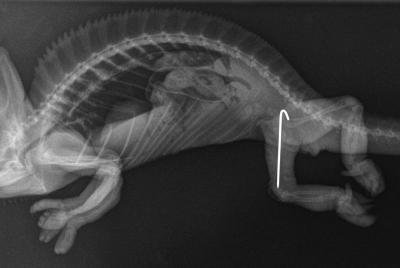

Operace zlomené nohy chameleona

Majitelka se s tímto chameleonem dostavila z důvodu zlomené nožičky. Jelikož jsme prohmatáním zjistili více míst, kde se osa dlouhých kostí láme, bylo vysloveno podezření na demineralizaci kostí. Na základě anamnézy byla za pravděpodobnou příčinu stanovena absence UVB lampy, protože bez UVB záření se neaktivuje vitamín D, který se podílí na ukládání vápníku do kostí.

Končetina po dokončené osteosyntéze. Hřeb vede skrz celou stehenní kost, v oblasti pánve vede ven z kosti a skrz kůži. Na povrchu těla je část hřebu zahnutá do tvaru háčku, aby nemohl hřeb vcestovat dovnitř.

RTG snímek fixované zlomeniny pravé stehenní kosti. Na snímku lze vidět, že levá stehenní kost je v pořádku.